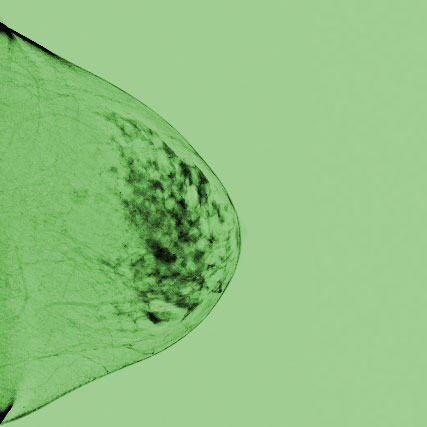

Vier Tage Intensivtraining in der Mammadiagnostik – Von der Einstelltechnik über MRT, Tomosynthese, Sono und Interventionen. Häufiges und Seltenes, Differentialdiagnose und Tipps zum Management: Der umfassende Kurs zur Mammadiagnostik für Einsteiger, Profis und solche, die es werden möchten.